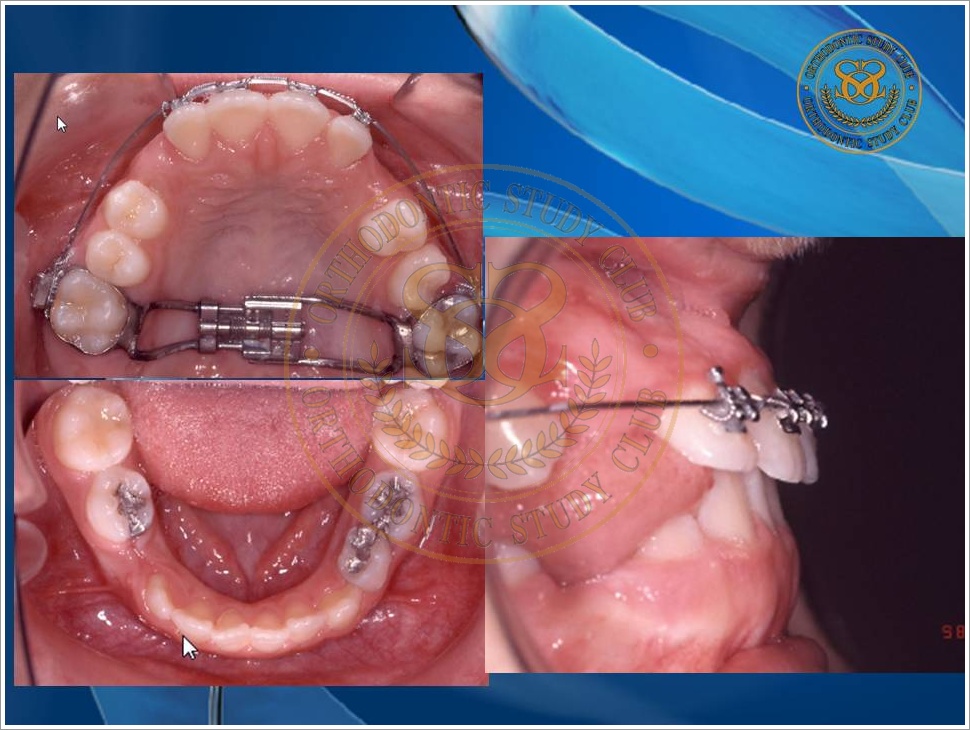

Treatment of Pseudo Class III (Class I Molar Relationship) and management of the embedded maxillary canine (Pt. Miss J.I.)